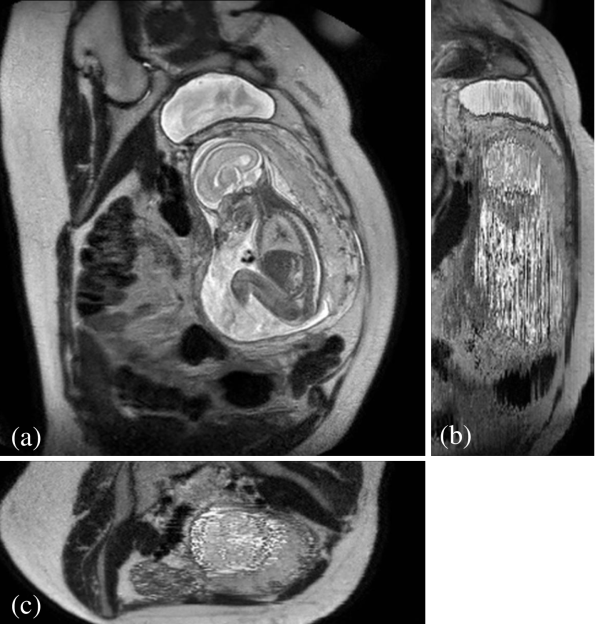

Reconstruction of Fetal Organs: Exemplary PVR and SVR reconstructions under motion introduced by kicking of the fetus are shown in Fig. 11. PVR reconstruction results show an improved visual appearance and less blurring in the region with severe motion artifacts (arrow). An example of a challenging clinical case with a kidney malformation in one of twin fetuses, is shown in Fig. 8. Our clinical partners confirmed that such complications are easier to examine and to quantify after PVR-based reconstruction.

Our method is able to automatically reconstruct whole collections of motion corrupted stacks without the need of image segmentations and manual identification of rigid regions. We have shown that PVR can reconstruct the whole uterus, selected fetal organs, and secondary, non-rigidly moving pregnancy structures such as the placenta.

In addition to reconstruction and motion correction of the whole uterus, we have also shown that our method works for multiple births cases with multiple fetuses sharing the same womb. These cases are more likely to have complications and to undergo MRI during pregnancy but would require extensive manual effort to be successfully reconstructed with state-of-the-art methods.

Reconstruction of large-scale anatomy: MRI has also been shown to be very useful for the evaluation of the whole uterus and structures like the placenta. During both, normal and high-risk pregnancies, the whole uterine appearance and the condition of the placenta are considered to be an indicator for fetal health after birth [18]. Placental functions affect the birth weight as it controls the transmission of nutrients from the maternal to the fetal circulation [19]. However, the whole fetal body and secondary uterine parts can be inherently inconsistent. Different fetal body parts can move independently from the uterus. This makes the application of SVR and 2D-3D registration to the full uterus impossible in the presence of fetal motion and maternal respiration.